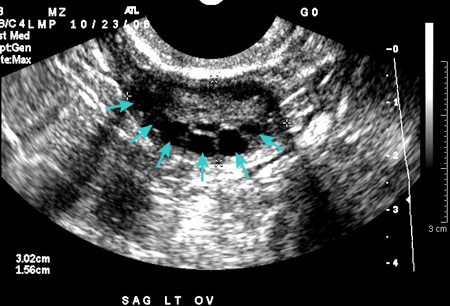

- Polycystic ovary syndrome (PCOS)